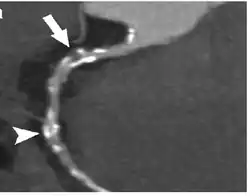

Coronary CT angiography (CTA or CCTA) is the use of computed tomography (CT) angiography to assess the coronary arteries of the heart. The patient receives an intravenous injection of radiocontrast and then the heart is scanned using a high speed CT scanner, allowing physicians to assess the extent of occlusion in the coronary arteries, usually in order to diagnose coronary artery disease.